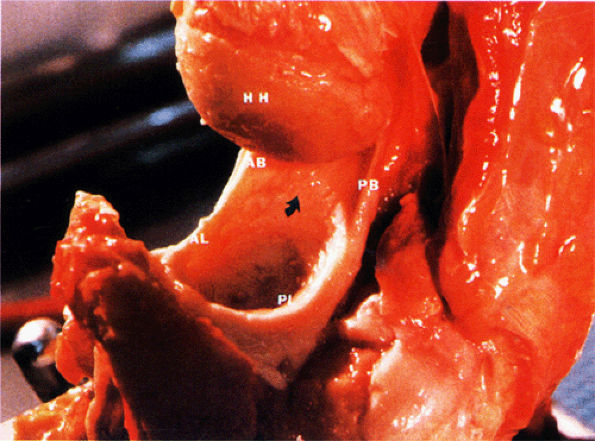

FIGURE 8.82 ● A gross shoulder specimen illustrates the structure of the inferior glenohumeral ligament (IGL) complex. With abduction of the humerus, the IGL structures are more prominent and taut in position. Coronal oblique MR images routinely show the lax axillary pouch of the IGL when the humerus is in the adducted position. Curved arrow, axillary pouch; AB, anterior band; AL, anterior labrum; HH, humeral head; PB, posterior band; PL, posterior labrum.